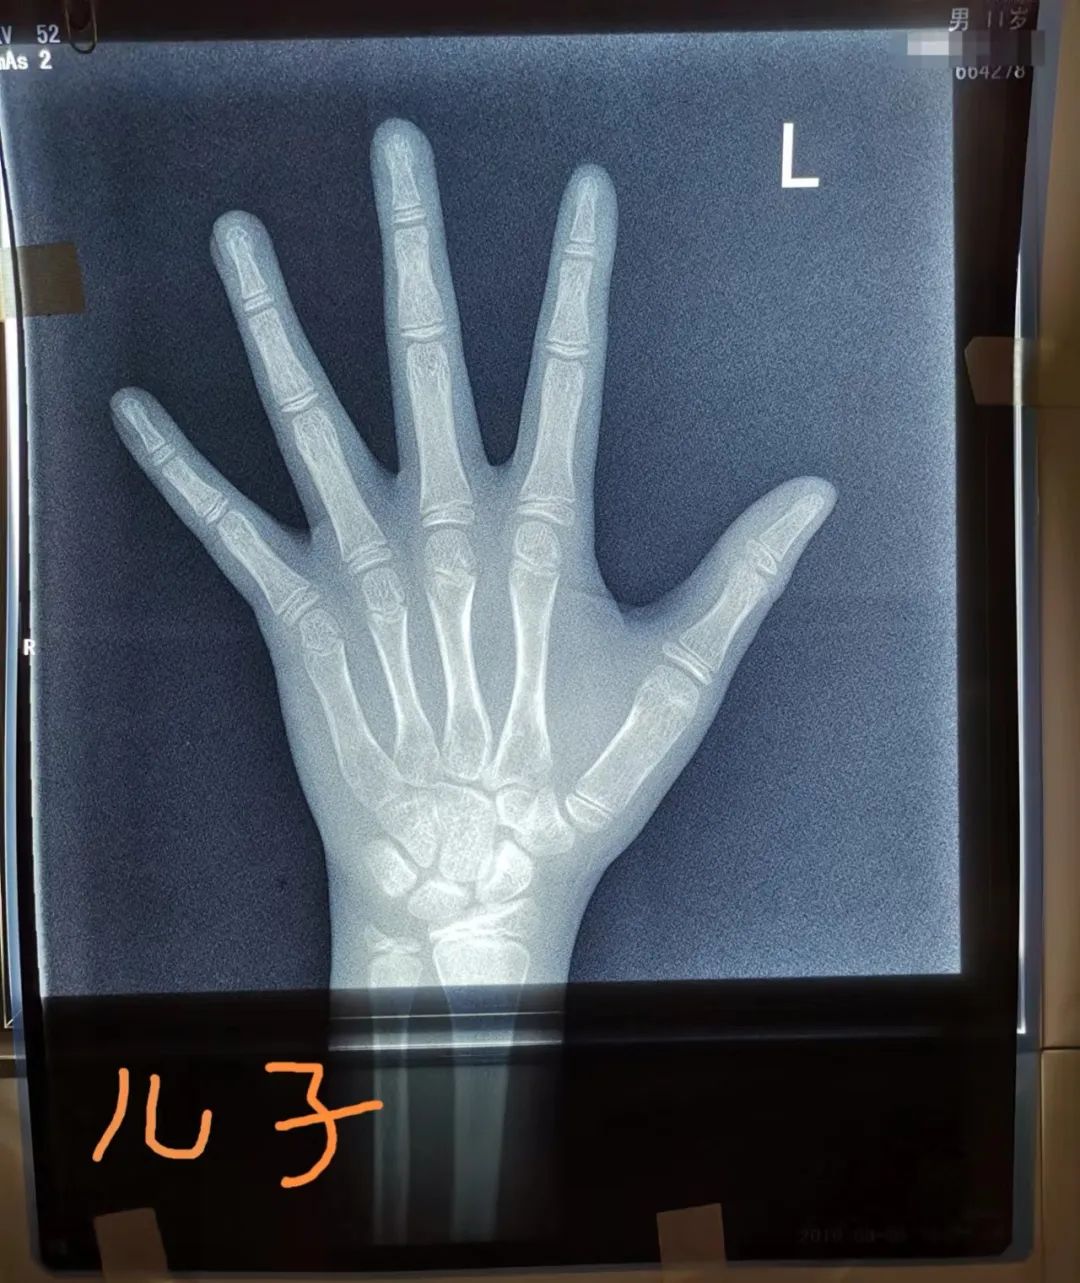

拍了三次骨龄片

10周岁那年,虽然两个孩子长得蛮好,在班上身高属于中等,但他们还是带孩子去了一家医院的儿科门诊,主动跟医生说要拍骨龄片。“主要是想看看骨龄有没有超前,能不能长到我们希望中那样高。”何女士说。

拍了骨龄片,测了父母和孩子的身高,最后电脑里吐出一张身高预测表,显示儿子终身高176.4厘米,女儿终身高157.7厘米。

半年后,何女士按照专家的要求,去复查,又拍了骨龄片。当时儿子身高155.2厘米,女儿146.9厘米,但这次预测的终身高降了:儿子175.9厘米,女儿154.7厘米。

“听医生说我儿子骨龄超了1.2岁,女儿超了0.5岁,一下又焦虑起来了。”何女士说。

黄轲主任医师说,最近门诊里最多的是来看身高的,其次是性早熟。前两天,门诊里来了对母子,妈妈有些焦虑。“医生,我儿子是不是性早熟了?以后是不是长不高了?”只见她翻出儿子的骨龄报告说,儿子今年11周岁,前不久刚拍了骨龄片,显示骨龄已13岁左右,当地医生说孩子的骨龄偏大了2岁,怀疑是性早熟。

黄轲主任看了孩子的骨龄片,又给孩子做了体格检查,孩子身高150厘米,偏胖,但睾丸还没有发育,没有出现性发育的迹象,不需要药物干预治疗。

“一般来说,在孩子发育早期,骨龄生长先启动,然后再是身高快速增长,最终两者持平。骨龄先于身高增长,很多孩子在发育早期,骨龄都是提前的。因此,不能单看一次骨龄情况来判断孩子的发育情况。在这个特殊时期,如果进行药物干预,不一定能得到很好的获益。” 黄轲说。

单凭骨龄并不能准确预测身高

不推荐常规检测骨龄

“不少家长不管孩子什么情况,到了门诊开口就要求给孩子先测个骨龄,但并不是每个孩子都有必要做骨龄检测。门诊中,真正需要测骨龄的大约只占2/3。也就是说,约有1/3的孩子无需做骨龄检测。”

黄轲主任医师说,经过评估,认为有性早熟、矮小或者和同年龄段正常的平均身高相差较大等异常情况的,才需要做骨龄检测。

“在门诊中,我们也碰到过一些家长,孩子只有两三岁,而且身高发育在正常平均水平范围内,也带着来测骨龄,这也是不科学的。因为低年龄段儿童正常骨发育存在较大的变异性,骨龄评估诊断价值有限,因此,6岁以下儿童不推荐常规检测骨龄。”

骨龄不是预测身高的唯一标准,不能单凭骨龄来判断孩子的终身高,遗传、营养、内分泌激素、疾病、生活环境等因素,都会影响终身高。

“目前骨龄可用于预测成年身高,但并没有任何一种方法能精确预测成年身高,其结果存在很大差异。”

影响骨龄的因素有很多,比如性早熟的孩子,下丘脑垂体被激活,激素水平上升,在雌激素的刺激下,骨龄进展会非常快,当骨龄进展速度超过年龄,就会导致身高的丢失。此外,肾上腺分泌的激素水平,也会促进骨龄进展。

黄轲认为,不能夸大了单次骨龄对身高预测的作用。尽管骨龄的规律性变化能比较好地反映儿童体格发育情况和生长潜力,但由于骨骼发育除受遗传因素影响外,也受到内分泌激素、炎症、营养状态、某些药物、应力作用等多因素影响,导致骨龄的进展呈现连续性、非匀速性、个体性的特点,因此单次骨龄检测只能反映该检测时间节点的发育状况,据此预测未来身高并不科学。